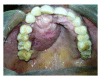

Neurofibroma is a benign peripheral nerve sheath tumor comprising variable mixture of Schwann cells, perineurial-like cells, and fibroblasts. Neurofibroma may occur as solitary lesion or as part of a generalised syndrome of neurofibromatosis or very rarely as multiple neurofibromas without any associated syndrome. There are two distinct variants of neurofibromatosis type I and type II. We present a case of neurofibroma of the hard palate associated with neurofibromatosis type I. The diagnosis of the lesion was made based on the clinical findings, family history, histopathology, and immunohistochemistry. Literature was reviewed and different types of neurofibroma, their incidence and frequency in the oral cavity, its association with neurofibromatosis, clinical manifestations, histopathologic characteristics, immunohistochemical analysis, behaviour, treatment, and recurrence are discussed.